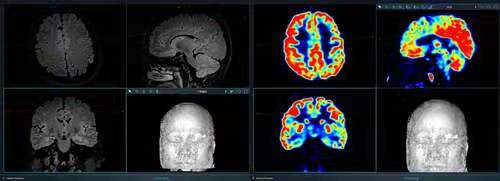

图1 头部磁共振和PET-CT  MRI未见明显癫痫病灶,但标识指示处存在异常脑沟及异常信号;PET-CT提示左侧大脑半球多处低代谢

患者入院后,医院癫痫MDT团队很快给患者完善了磁共振癫痫序列、PET-CT和视频脑电图(图1)。入院观察也很快发现患者的临床表现并非她描述的左侧肢体不受控制的抽动,而是左上肢强直以及过度运动II型。但磁共振和PET-CT结果并未发现明确的癫痫病灶,这也是所谓的磁共振阴性癫痫。结合上述结果,团队再次组织了MDT会诊,专家们共同认为患者存在癫痫局灶起源可能,并将范围缩小在大脑纵裂深面某些区域,建议下一步进行Seeg(立体定向脑电图)来锁定隐藏的癫痫病灶。Seeg是目前癫痫领域探索癫痫起源及癫痫病变范围的最先进且最高端的检查手段,它将一定数量的颅内电极植入到脑内相应区域,从时间和空间上充分了解癫痫放电情况,以便指导制定精准有效的治疗方案。饱受疾病困扰的患者充分了解癫痫MDT的会诊意见后,强烈要求完善Seeg检查,患者似乎终于在长期笼罩生活的阴霾中感受到了一丝曙光。